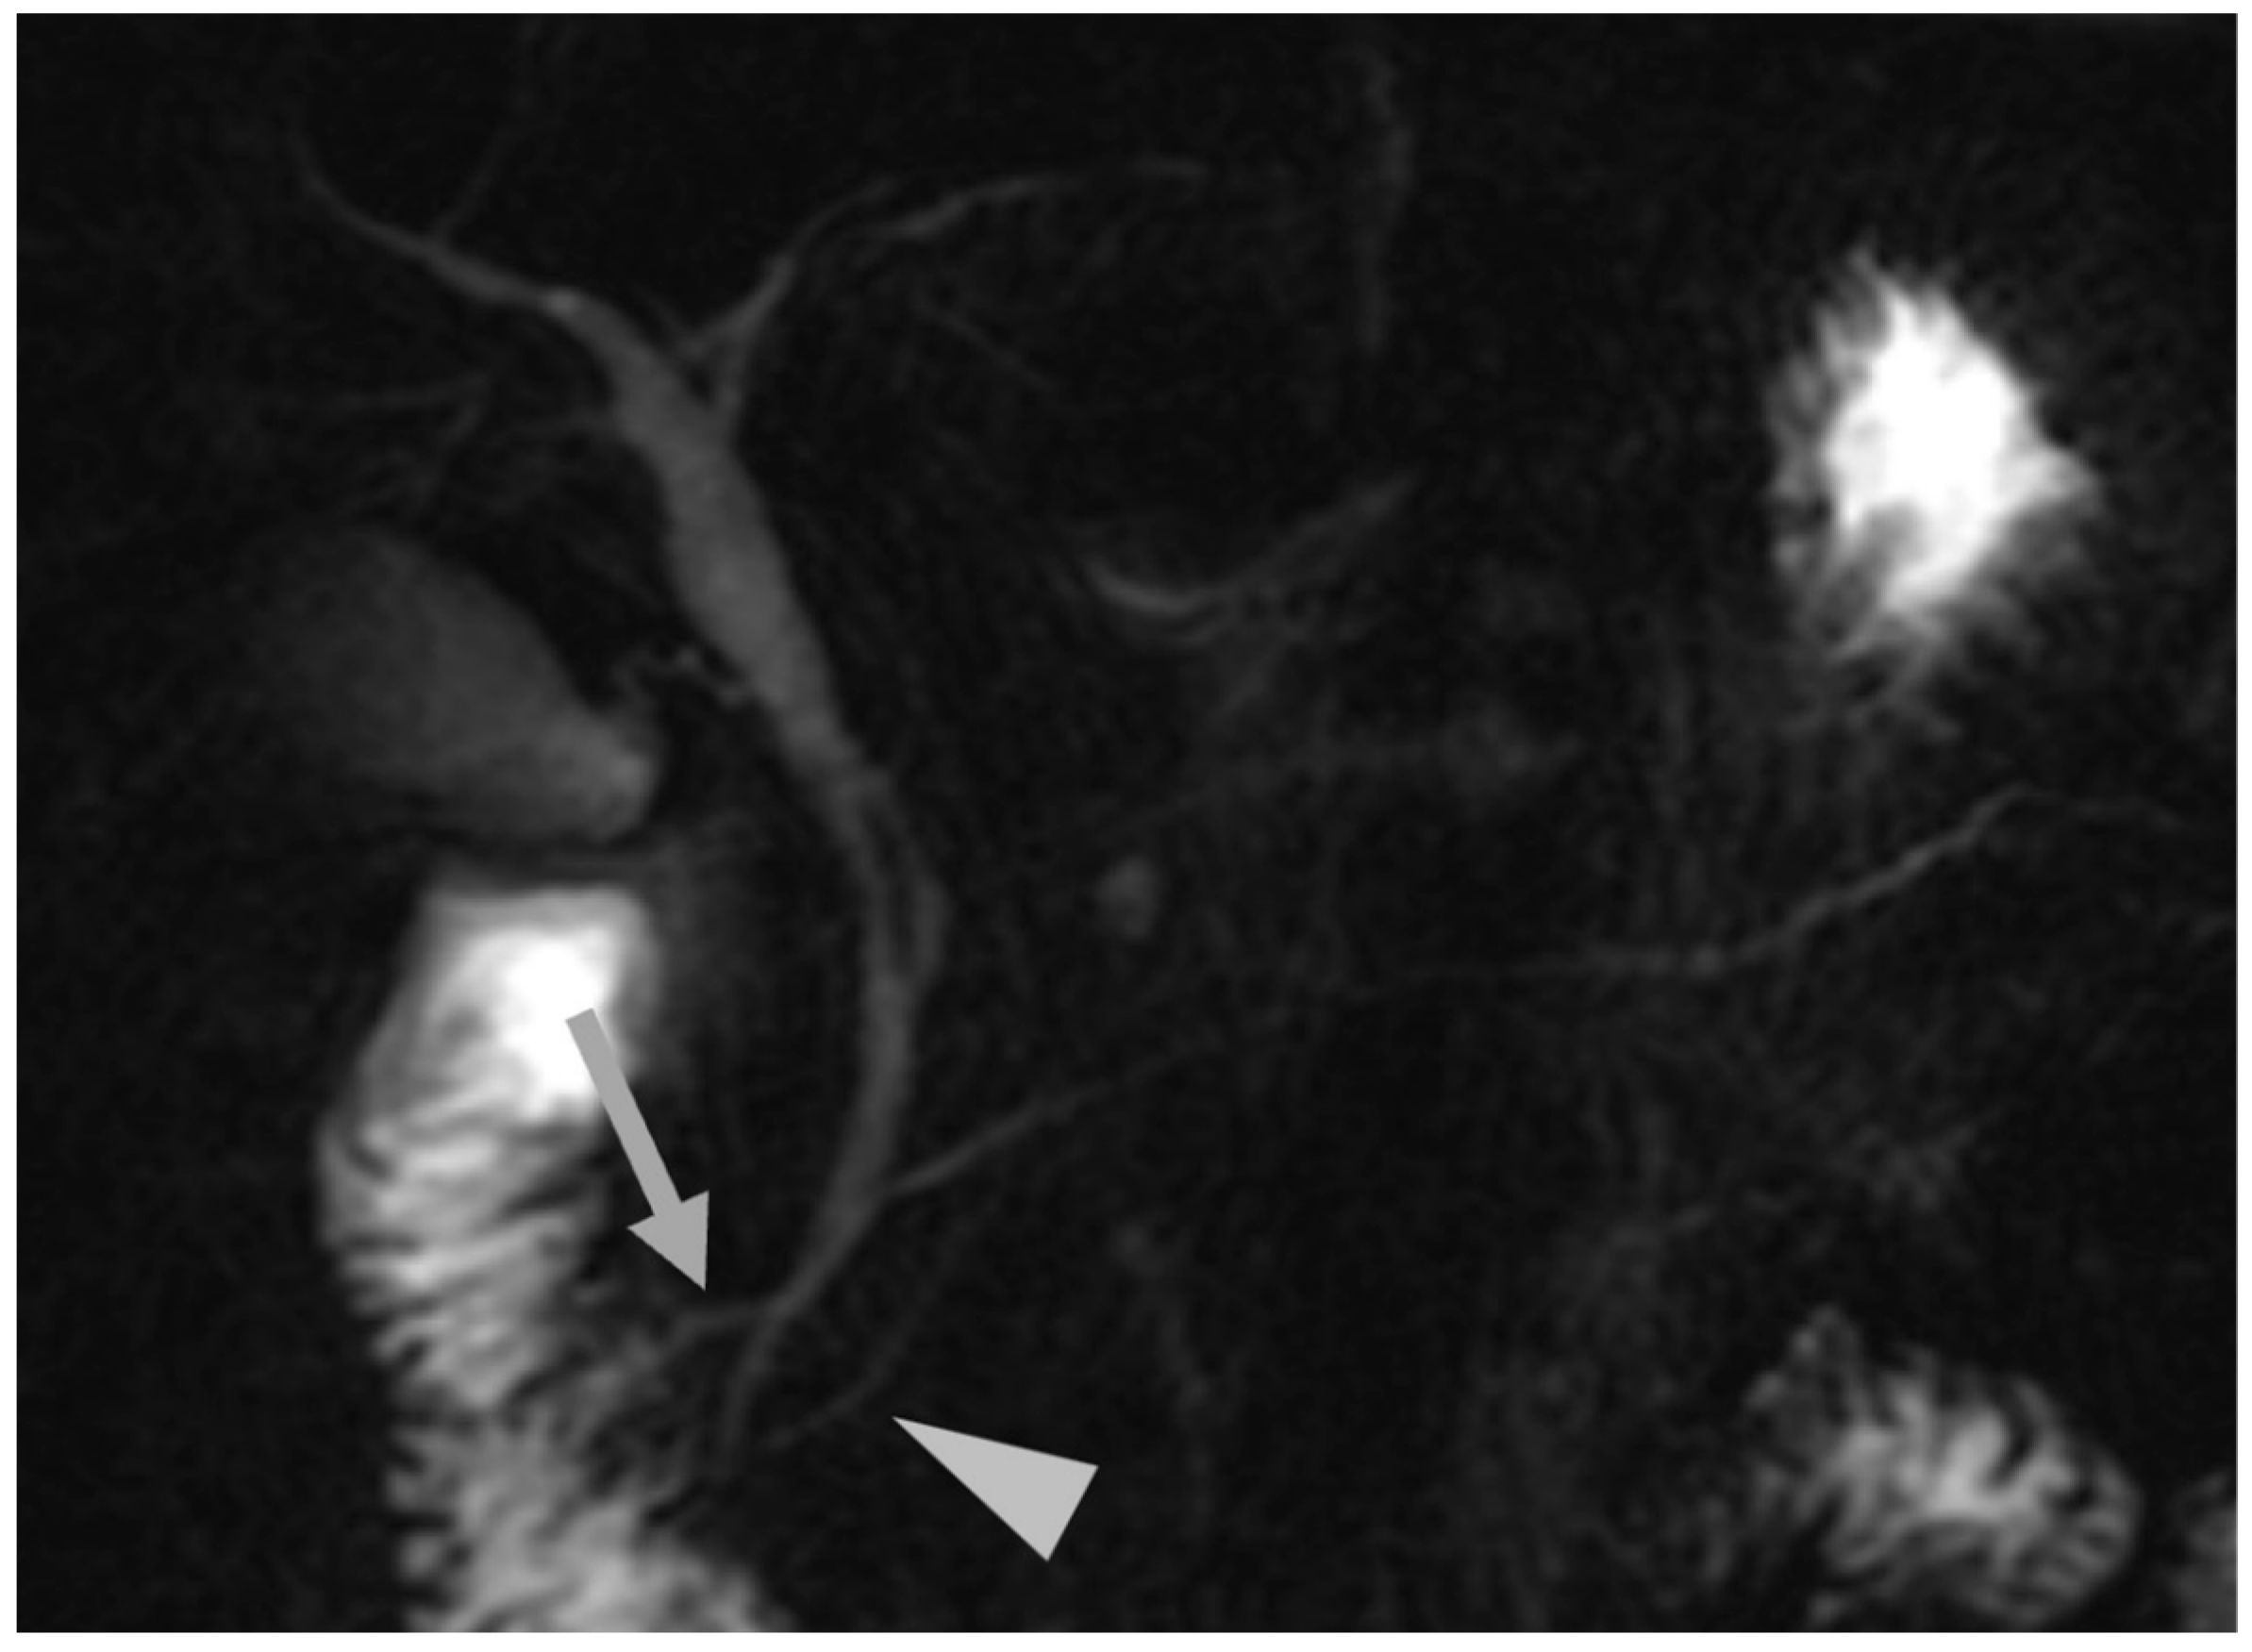

- EUS is a valuable tool for diagnosing pancreas divisum, a common congenital anomaly of the pancreatic duct. Several studies have evaluated its diagnostic yield, demonstrating a sensitivity ranging from 51% to 95% and a high diagnostic accuracy of 97% [40]. MRCP’s sensitivity for comparison with EUS in detecting PD has been reported between 44% and 60%. EUS is particularly effective in identifying pancreas divisum structural features, such as the dorsal pancreatic duct draining into the minor papilla without communication with Wirsung’s duct. This is when the ventral and dorsal ducts fail to fuse during embryogenesis and dominant drainage occurs via the minor papilla (Figure 1).

- Three endosonographic criteria have been suggested for the diagnosis of pancreas divisum with endoscopic ultrasound: (a) Inability to follow the main pancreatic duct from the major ampulla to the pancreas body; (b) Inability to follow the main PD from the hypoechoic ventral pancreas to the hyperechoic dorsal pancreas [40]; (c) The presence of the Stack sign as a possibility of pancreas divisum. The Stack sign is visualized better by positioning the radial echoendoscope (or by linear echoendoscope, reverse Stack sign) in the long scope position with the transducer in the duodenal bulb. When the balloon is inflated and advanced snugly into the apex of the bulb, the bile duct (closest to the transducer) and the pancreatic duct can be seen running in parallel through the pancreatic head [26,41]. Performing EUS, the Stack sign refers to the parallel alignment of three tubular structures seen in the region of the pancreatic head: common bile duct (CBD), ventral pancreatic duct (Wirsung’s duct), and dorsal pancreatic duct (Santorini’s duct). In pancreas divisum (positive Stack sign): the ventral and dorsal pancreatic ducts remain separate and on EUS, three parallel, stacked tubular structures are evident: (a) the CBD (most anterior); (b) the ventral pancreatic duct (Wirsung); (c) the dorsal pancreatic duct (Santorini) (most posterior). This triple-duct alignment is indicative of non-fusion and suggests pancreas divisum.